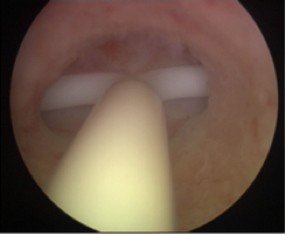

• Гистероскопия